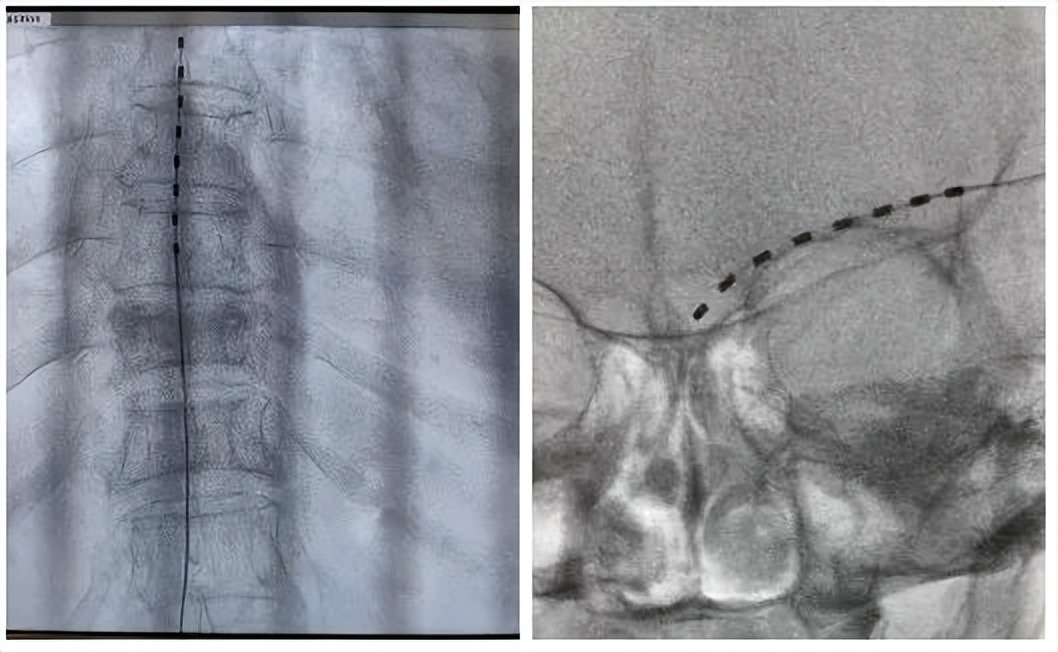

对于带状疱疹后神经痛的患者,使用微创技术,用一根穿刺针,将电极置入脊髓相应节段或外周病变神经处,对病变神经进行精准电调控,手术时间短、痛苦少、效果好。

脊柱经根卡压松解术,等离子髓核消融术

用一根针穿刺到被卡压的脊神经处,对该处的神经进行松解、调控,起到松解神经,缓解疼痛的作用。